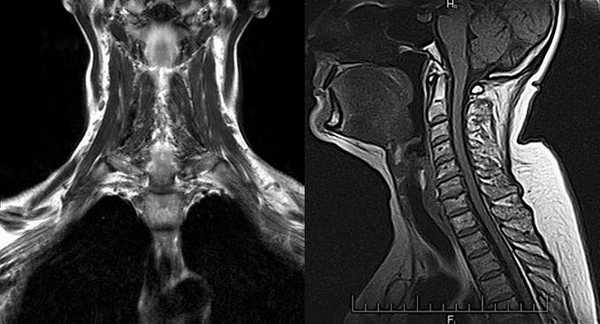

Материалы и методы. МСКТ-исследования полости рта и ротоглотки проводились на аппарате Bright Speed 16 (General Electric). Сканирование выполнялось в спиральном режиме с толщиной томографического среза 2,5 мм, с шагом томографирования 2,5 мм до и поcле внутривенного болюсного введения контрастного вещества. Контрастное усиление достигалось путем введения 100 мл неионного контрастного вещества при скорости введения 3 мм/сек, время задержки сканирования 40 секунд. Зона сканирования включала в себя область от основания черепа до яремной вырезки. Сырые данные повторно реконструировали с шагом реконструкции 1.25 мм. В последующем выполнялось построение многоплоскостных реформаций изображений (МРR) на рабочей станции. МРТ проводилась на аппарате «Excelart Vantage» 1,5 Т (Toshiba). Исследования дна полости рта методом МРТ проводилось в режимах Т1-ВИ, Т2-ВИ, STIR в сагиттальной, коронарной и трансверзальной проекциях с толщиной среза 5 мм с использованием шейной катушки. В исследовании участвовали 50 пациентов (45 мужчин, 5 женщин) в возрасте от 41 до 73 лет. Результаты во всех случаях сопоставлялись с данными, полученными при патогистологических и интраоперационных исследованиях.

Особенностью МРТ являлась высокая контрастность мягких тканей. Плотные костные ткани или зубоврачебный материал не создавали артефактов, что давало возможность получать четкое изображение опухоли полости рта, определять распространение в мягкие ткани, глубокие отделы орофарингеальной зоны, в область неба. На Т1-ВИ все опухоли имели ту же интенсивность сигнала, как у окружающих мышц или слабее (рис.7).

Рис.7. Пациент С., 55 лет. МРТ ротоглотки в сагиттальной проекции в режиме Т1-ВИ. Опухоль дна полости рта с переходом на нижнюю поверхность языка (стрелки)

После введения контрастного вещества все опухоли показывали усиление сигнала. При локализации опухолевого процесса в области языка (12 пациентов) границы опухоли визуализировались более четко. В режиме Т2-ВИ опухолевые узлы проявлялись более высокой интенсивностью сигнала, чем у окружающих мышц (рис. 8).

Рис. 8. Пациент П., 76 лет. МРТ полости рта в сагиттальной проекции в режиме Т2-ВИ. Опухоль языка, высокая интенсивность сигнала на фоне окружающих мышц (стрелки)

Рис. 9. Пациент А., 66 лет. МРТ дна полости рта в сагиттальной проекции в режиме Т2-ВИ. Опухоль дна полости рта размерами 2,0х1,8 см с распространением на основание языка Т1N0M0 (стрелки). Границы опухоли четко визуализируются, структура однородная